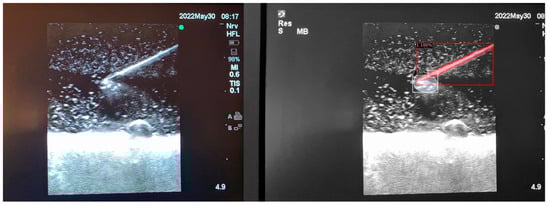

3.4. Inaccuracies in Distorted Images

While we continue to expand our training image pool and refine the deep learning process, we have identified a few key shortcomings with the automated detection of distorted or low quality images. Low quality ultrasound images can be defined as images with unclearly visualised structures (partially occluded or distorted vessels or needles, lack of clear delineation between structure and background) or those with noisy backgrounds (hyper or hypoechogenic depending on probe angulation, gain and scale settings, type of phantom model). Our deep learning algorithm is still able to identify the presence of the target structures with striking accuracy, but can mislabel surrounding noise as additional structures (Figure 7A,B).

Figure 7. (A,B) Poor image quality leading to unclear identification of target structures.